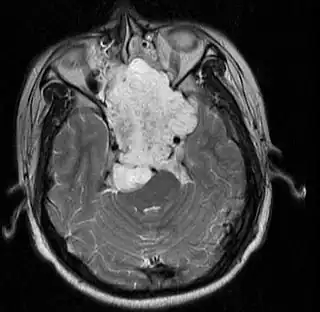

Imagen de RMN de un cordoma en un varón de 17 años, vista axial. | ||